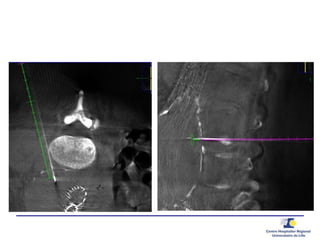

Ponction translombaire –

embolisation directe

Ponction

Anévrysmographie

Guide de pression 0.014’’

20 G needle0.014’’ PressureWire

 Pression

Aorta

Sac